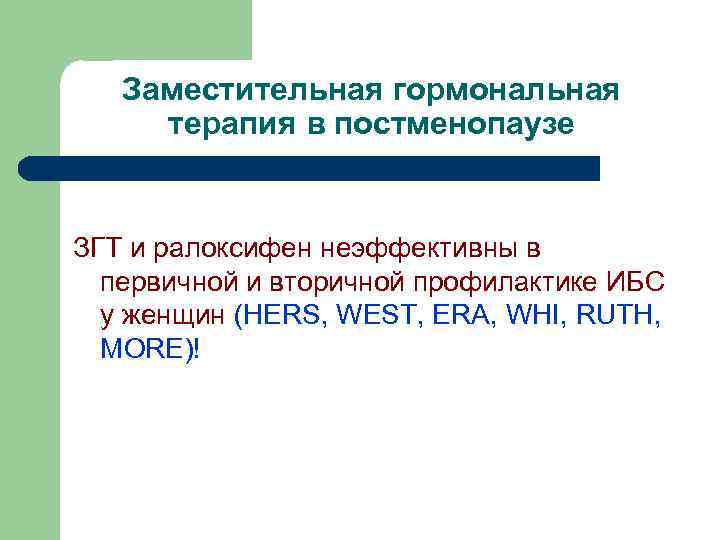

Заместительная гормональная терапия в постменопаузе ЗГТ и ралоксифен неэффективны в первичной и вторичной профилактике ИБС у женщин (HERS, WEST, ERA, WHI, RUTH, MORE)!